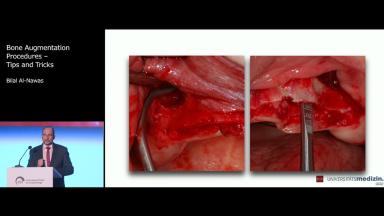

Bone Augmentation Procedures – Tips and Tricks

Bilal Al-Nawas

This lecture deals with different types of bone defects and discusses how those defects might be reconstructed. Indications for use of bone substitutes and different types of barrier membranes are also presented. Particular attention is paid to the reconstruction of extrabony defects by means of the bone split technique, sandwich osteoplasty or use of block grafts. Application of custom-fabricated CAD/CAM mesh and different types of incisions and flaps for bone reconstruction are also presented. Finally, the most common complications in bone reconstruction and their etiology are discussed.